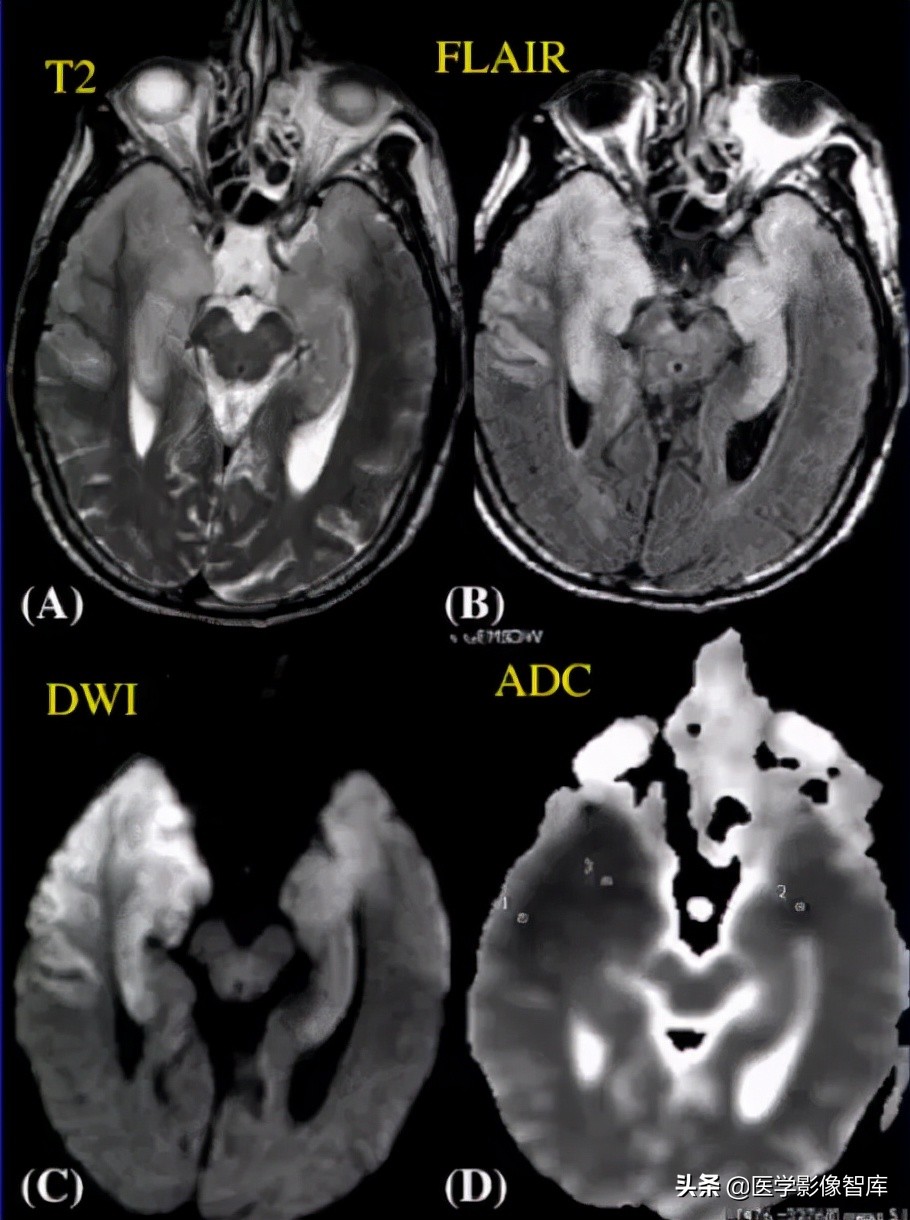

脑炎(包括病毒性脑炎、自身免疫性脑炎等)都有可能出现累及皮层 / 皮层下的 DWI 高信号。脑炎一般不难鉴别,急性起病,有发热、头痛等症状。累及皮层的脑炎会出现癫痫发作、精神症状等,行腰穿查脑脊液常规、生化、病毒抗体、自身免疫性脑炎抗体等可帮助诊断,图 1 为单疱脑炎患者发病 6 天时的磁共振检查结果。

图 1 单疱脑炎,起病 6 天,可见两侧颞叶病灶,右侧为甚,T2WI、FLAIR、DWI 均为高信号,ADC 图为低信号